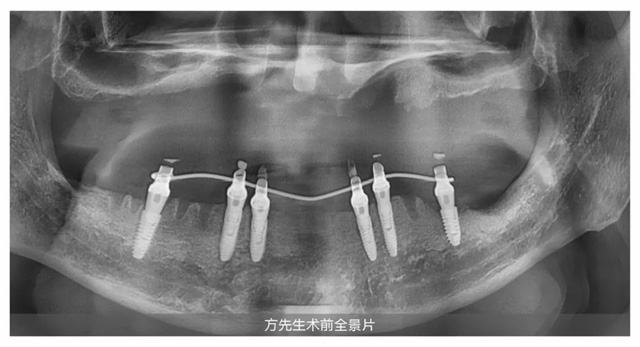

經檢查,方先生因為長期缺牙,牙槽骨萎縮較為嚴重,確實需要植骨治療來增加牙槽骨的穩定性和支撐性,為種植牙“扎根”提供條件。但王鋒醫生表示:“從手術操作的角度來看,植骨和種植體植入可同步進行。這樣可以避免顧客重復手術和麻醉的痛苦,有效節省時間和費用。”王醫生的話,對方先生來說猶如天籟:“看過那么多醫生,只有王鋒醫生非常肯定地告訴我可以當天植骨,當天種牙。”說這話時的方先生仿佛還沉浸在當初的喜悅中。

定下方案第三天,方先生在新橋口腔接受了上半口即刻種植。王鋒醫生在方先生上頜同時完成骨粉和7顆種植體植入,當天為他戴上臨時牙冠,成功解決了困擾方先生許久的缺牙問題。成功圓夢的方先生稱贊道:“只有即刻植骨即刻種植,才是真正的好。”